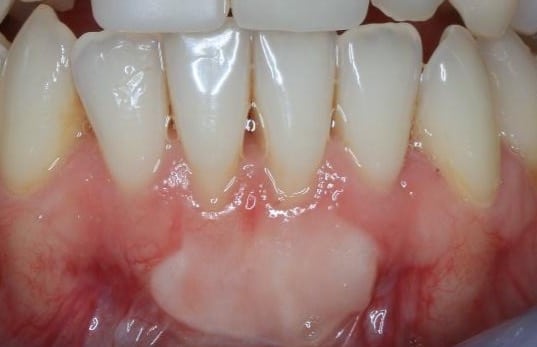

Free gingival grafts

This surgical technique first described by Bjorn 1963, and later modified by Sullivan and Atkins in 1968, is commonly used for mandibular recessions where aesthetic concerns are of less importance. The colour match to the surrounding gingival tissue is unpredictable, however this method is a predictable surgical technique to primarily increase keratinised tissue width. Some root coverage may be achieved. Over time a ‘creeping attachment mechanism’ can occur. This attachment results in the post-operative migration of the free gingival graft in a coronal direction, thereby increasing root coverage over time. Both surgical techniques can also be used around implants.

Figure 3. An epithelialised free gingival graft to increase keratinised tissue width.